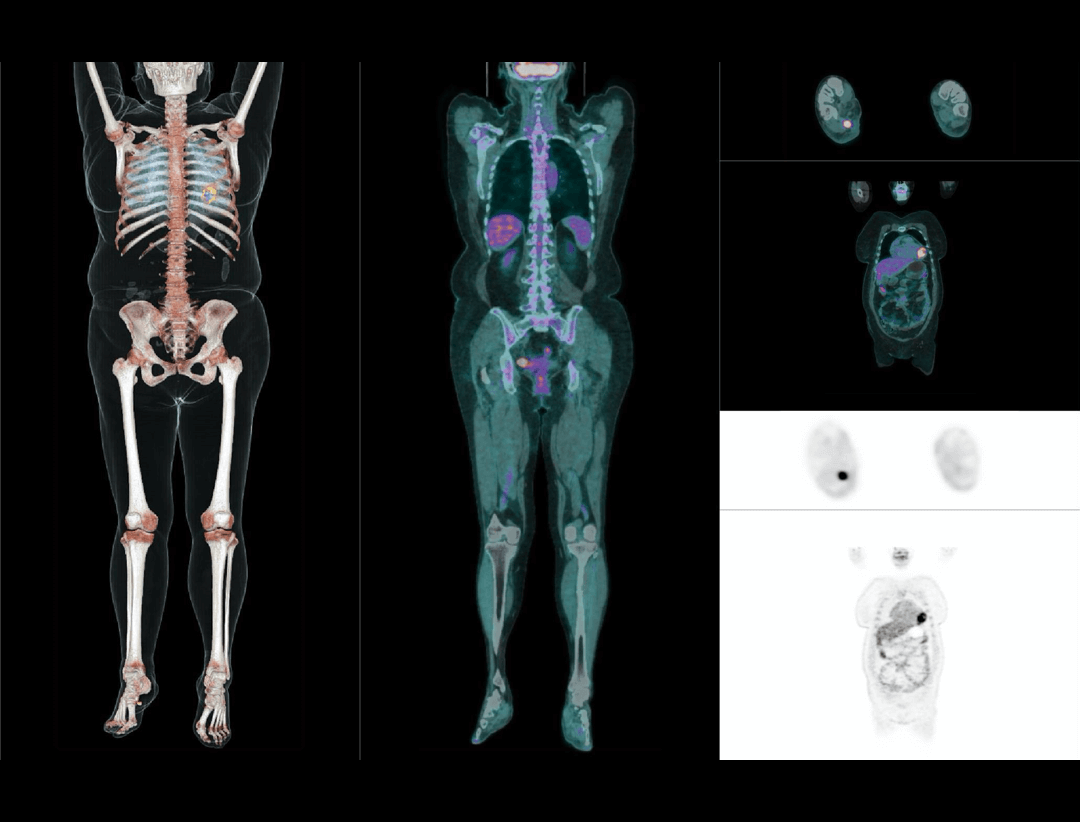

업계 최고수준의 감도

광자 감지 효율 증가

높은 영상 품질로 Low dose 이미징 가능

Ultra-large axial FOV를 통한 Whole organ 이미징

eye-to-thigh 스캔

전신 스캔 시 5분 이내의 신속한 속도로 진행